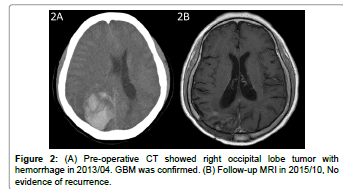

Sirolimus and Hydroxychloroquine as an Add-On to Standard Therapy for Glioblastoma Multiforme: Case Report